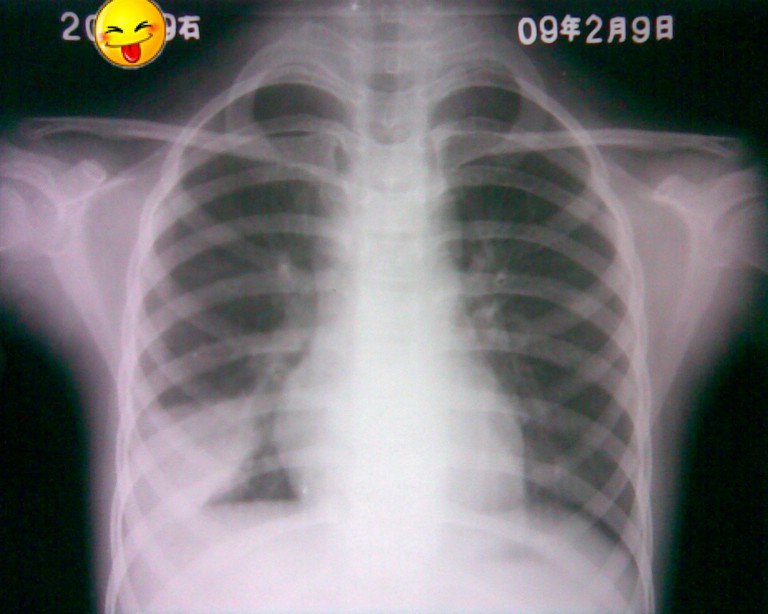

标题: PED1836:女,9岁,发热5天,听诊两肺呼吸音粗 [打印本页]

标题: PED1836:女,9岁,发热5天,听诊两肺呼吸音粗

治疗的挺好

不错,疗效看得见。

炎性,疗效看得见。

节段性肺炎。典型!

节段性肺炎。典型!!!

节段性肺炎。片资料完整。